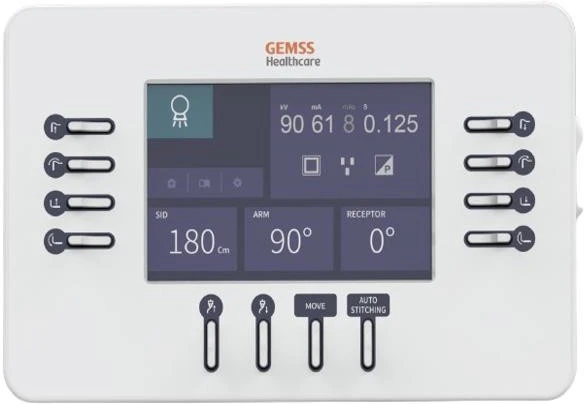

- Интуитивно понятное управление: Простая в использовании система управления, что сокращает время на обучение персонала.

Автоматическая сшивка изображений одним нажатием. Разрешение 250 мкм, что дает возможность видеть минимальыне объекты исследования. Автоэкспозиция исключает ошибки лаборанта. Функция Smart stitch позволяет делать сшивку без потери информации при итоговом снимке. Протокол работы с контрастом не допускает пересвета снимков.

Интеграция с DICOM Worklist для автоматизированного выбора параметров. Возможность сохранения персонализированных настроек изображений.